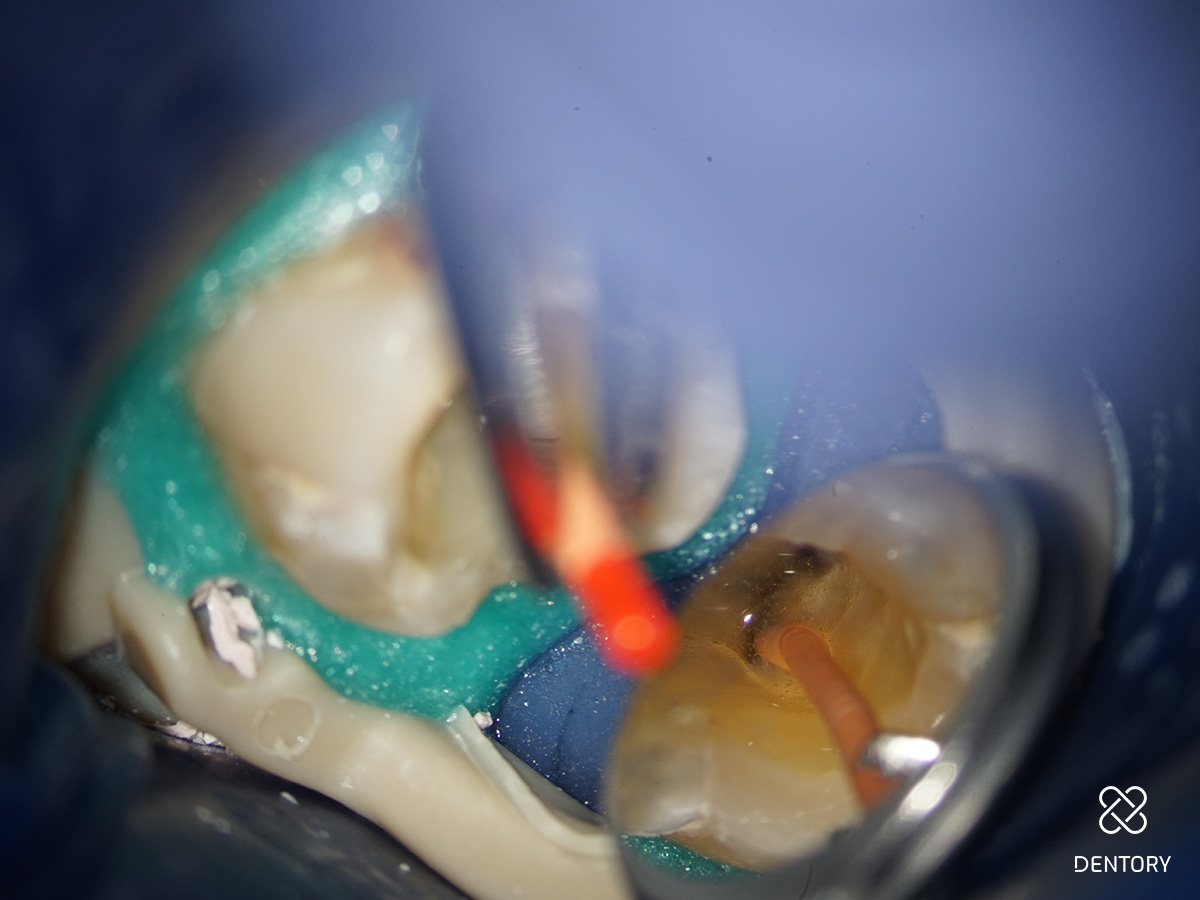

Abbildung 3

Aufbereitung des distalen Kanals: Es ist darauf zu achten, die Kontaktzeit im Kanal kurz zu halten sowie den Kanal abschnittsweise von koronal nach apikal zu bearbeiten. Zusätzlich verhindert eine regelmäßige Rekapitulation mit einer Handfeile bis zur endometrisch bestimmten Länge eine Verblockung des Kanals mit Debris.